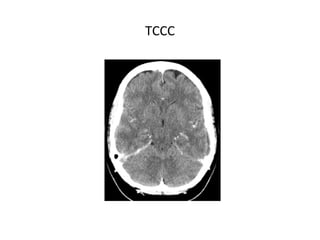

TCCC

SIGNOS INDIRECTOS

- Infartos no hemorrágicos: Frecuentes. (subcortical, sin

distribución arterial típica, proximal al seno afectado).

- Infartos hemorrágicos: 10-50% de los casos, pueden ser

profundos, superficiales o multifocales.

- Edema cerebral difuso.

- Colapso ventricular.